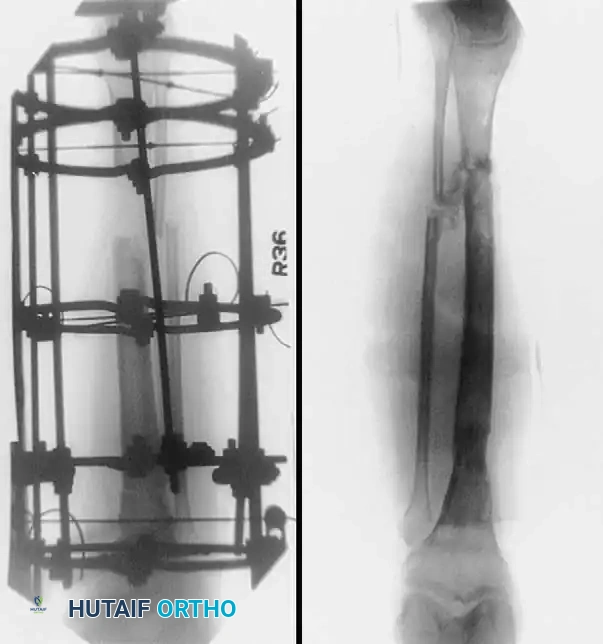

Advanced Surgical Technique: Circular External Fixation

While IM nailing is ideal for diaphyseal fractures, external fixation—particularly circular ring fixators (Ilizarov or Taylor Spatial Frame principles)—is invaluable for severe open fractures, highly comminuted metaphyseal-diaphyseal fractures (AO Type C), and fractures with extensive periarticular involvement.

Step 6: Distraction Ligamentotaxis for AO Type C Injuries

For severe AO Type C injuries with extensive joint involvement, massive metaphyseal comminution, or bone loss, standard reduction techniques may fail. In these scenarios, distraction ligamentotaxis is employed.

- It is highly helpful to preconstruct a four-ring frame with an attached foot frame to maintain distraction at the ankle joint.

- The distraction construct can be as simple as a single calcaneal transfixation pin/wire attached to a distal calcaneal half-ring, or as extensive as a full foot frame attached to the distal tibial ring.

- Attach the proximal tibial rings first, ensuring appropriate soft-tissue clearance (minimum two fingerbreadths) to accommodate postoperative edema.

- Attach the foot frame or calcaneal pin, and perform distraction ligamentotaxis across the ankle joint by adjusting the threaded rods. The tension of the intact joint capsule and ligaments will pull the comminuted articular fragments into alignment.

Clinical Pearl: Open Reduction in Ligamentotaxis

If ligamentotaxis reduction is inadequate (often due to impacted osteochondral fragments or interposed soft tissue), do not over-distract. Perform a limited open procedure to disimpact the fragments directly.

- When reduction is satisfactory, position the distal tibial ring at the level of the fracture. Pass the fixation wires across the fracture fragments, attach them to the ring, and tension them.

- Note: The only difference in this specific technique is that the distal tibial ring is already attached to the preconstructed frame, so it is not necessary to "clamshell" the ring to place it around the wires.

Postoperative Protocol and Complications

Postoperative management is dictated by the fracture pattern, soft-tissue envelope, and the stability of the chosen fixation.

For intramedullary nails in stable patterns, immediate weight-bearing as tolerated is often permitted. For circular frames, weight-bearing is encouraged to promote micromotion at the fracture site, which stimulates secondary bone healing (callus formation). Meticulous pin site care is mandatory to prevent superficial infections

Associated Surgical & Radiographic Imaging